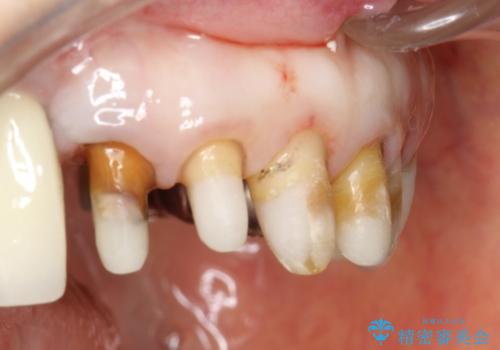

- 歯周外科・再根管治療後、クラウンを製作する。

時間をかけ、妥協なく治療を行い、今後の再治療の可能性を極力少なくするために、

費用や時間といった労力がかかってしまうのは当然のことです。

かぶせ物の種類:PFZ standard